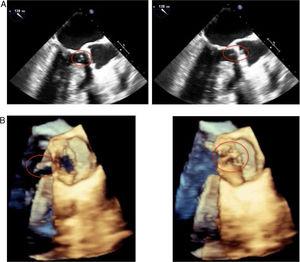

Given the high suspicion of aortic prosthetic valve endocarditis (PVE) despite the negative echocardiogram, an 18F-FDG PET/CT was requested because of the high sensitivity and specificity of this technique for diagnosing PVE. To reduce the myocardium physiological uptake of 18F-fluorodeoxyglucose (18F-FDG), the patient was prepared with a high-fat, low-carbohydrate meal and fasted for 18 hours.

The images revealed an intense hyper-metabolism confined to the aortic annulus, above the aortic-valve prosthesis, with inhibition of the rest of the cardiac metabolism after the prescribed preparation. This confirmed the diagnosis of aortic PVE, with no evidence of pathological deposits of tracer in the mitral valve or other body territories (Figure 2).

18F-fluorodeoxyglucose positron emission tomography/computed tomography reveals intense hyper-metabolism confined to the aortic annulus, above the aortic valve prosthesis, with inhibition of the rest of the cardiac metabolism, with no evidence of pathological deposits of the tracer in other body territories.